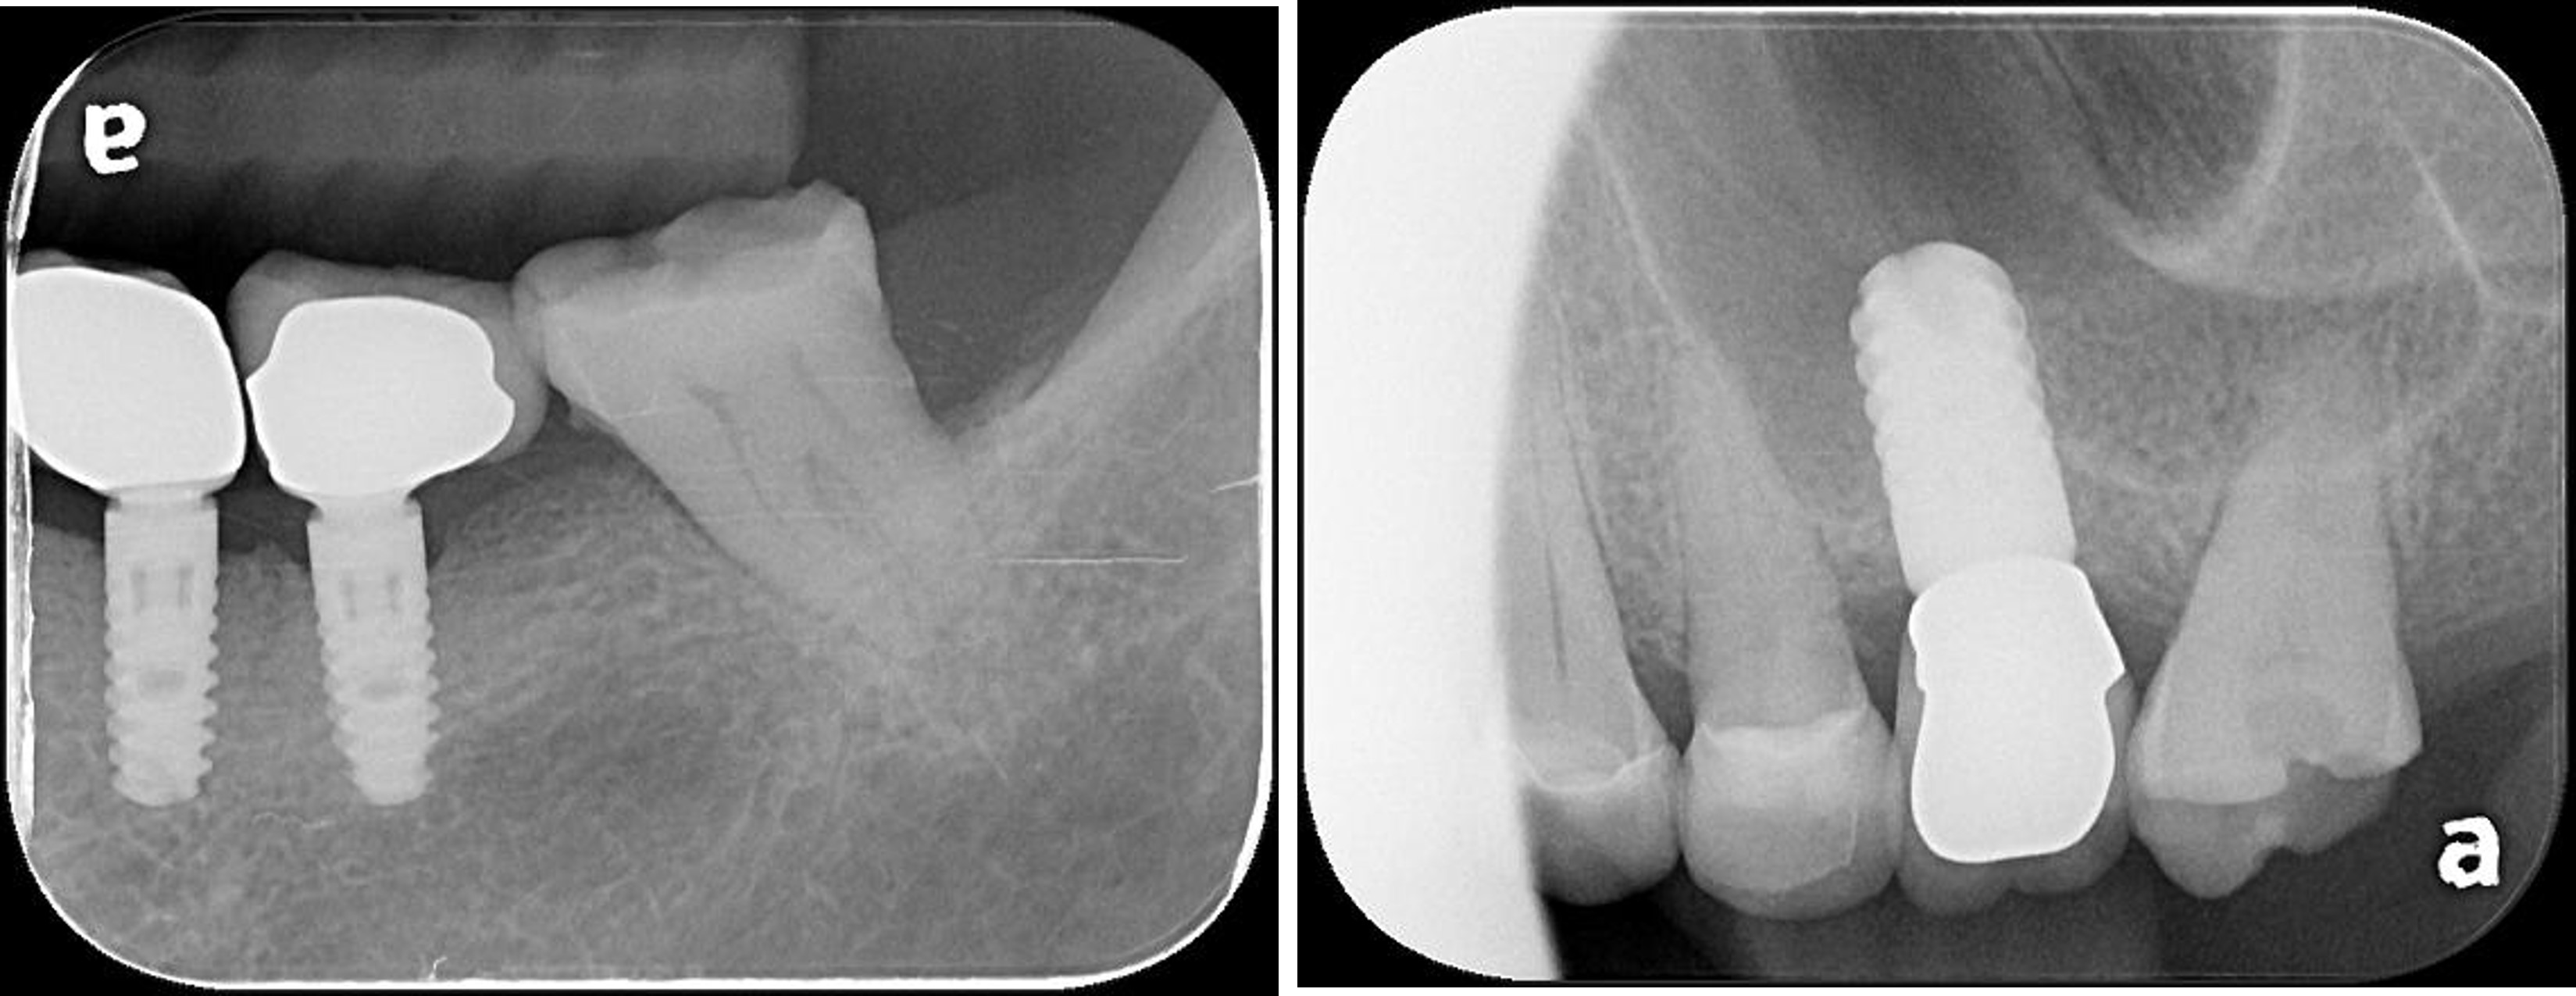

治療前,左上及左下第二大臼齒根管鈣化

顯微根管治療:#37

顯微根管治療:#27